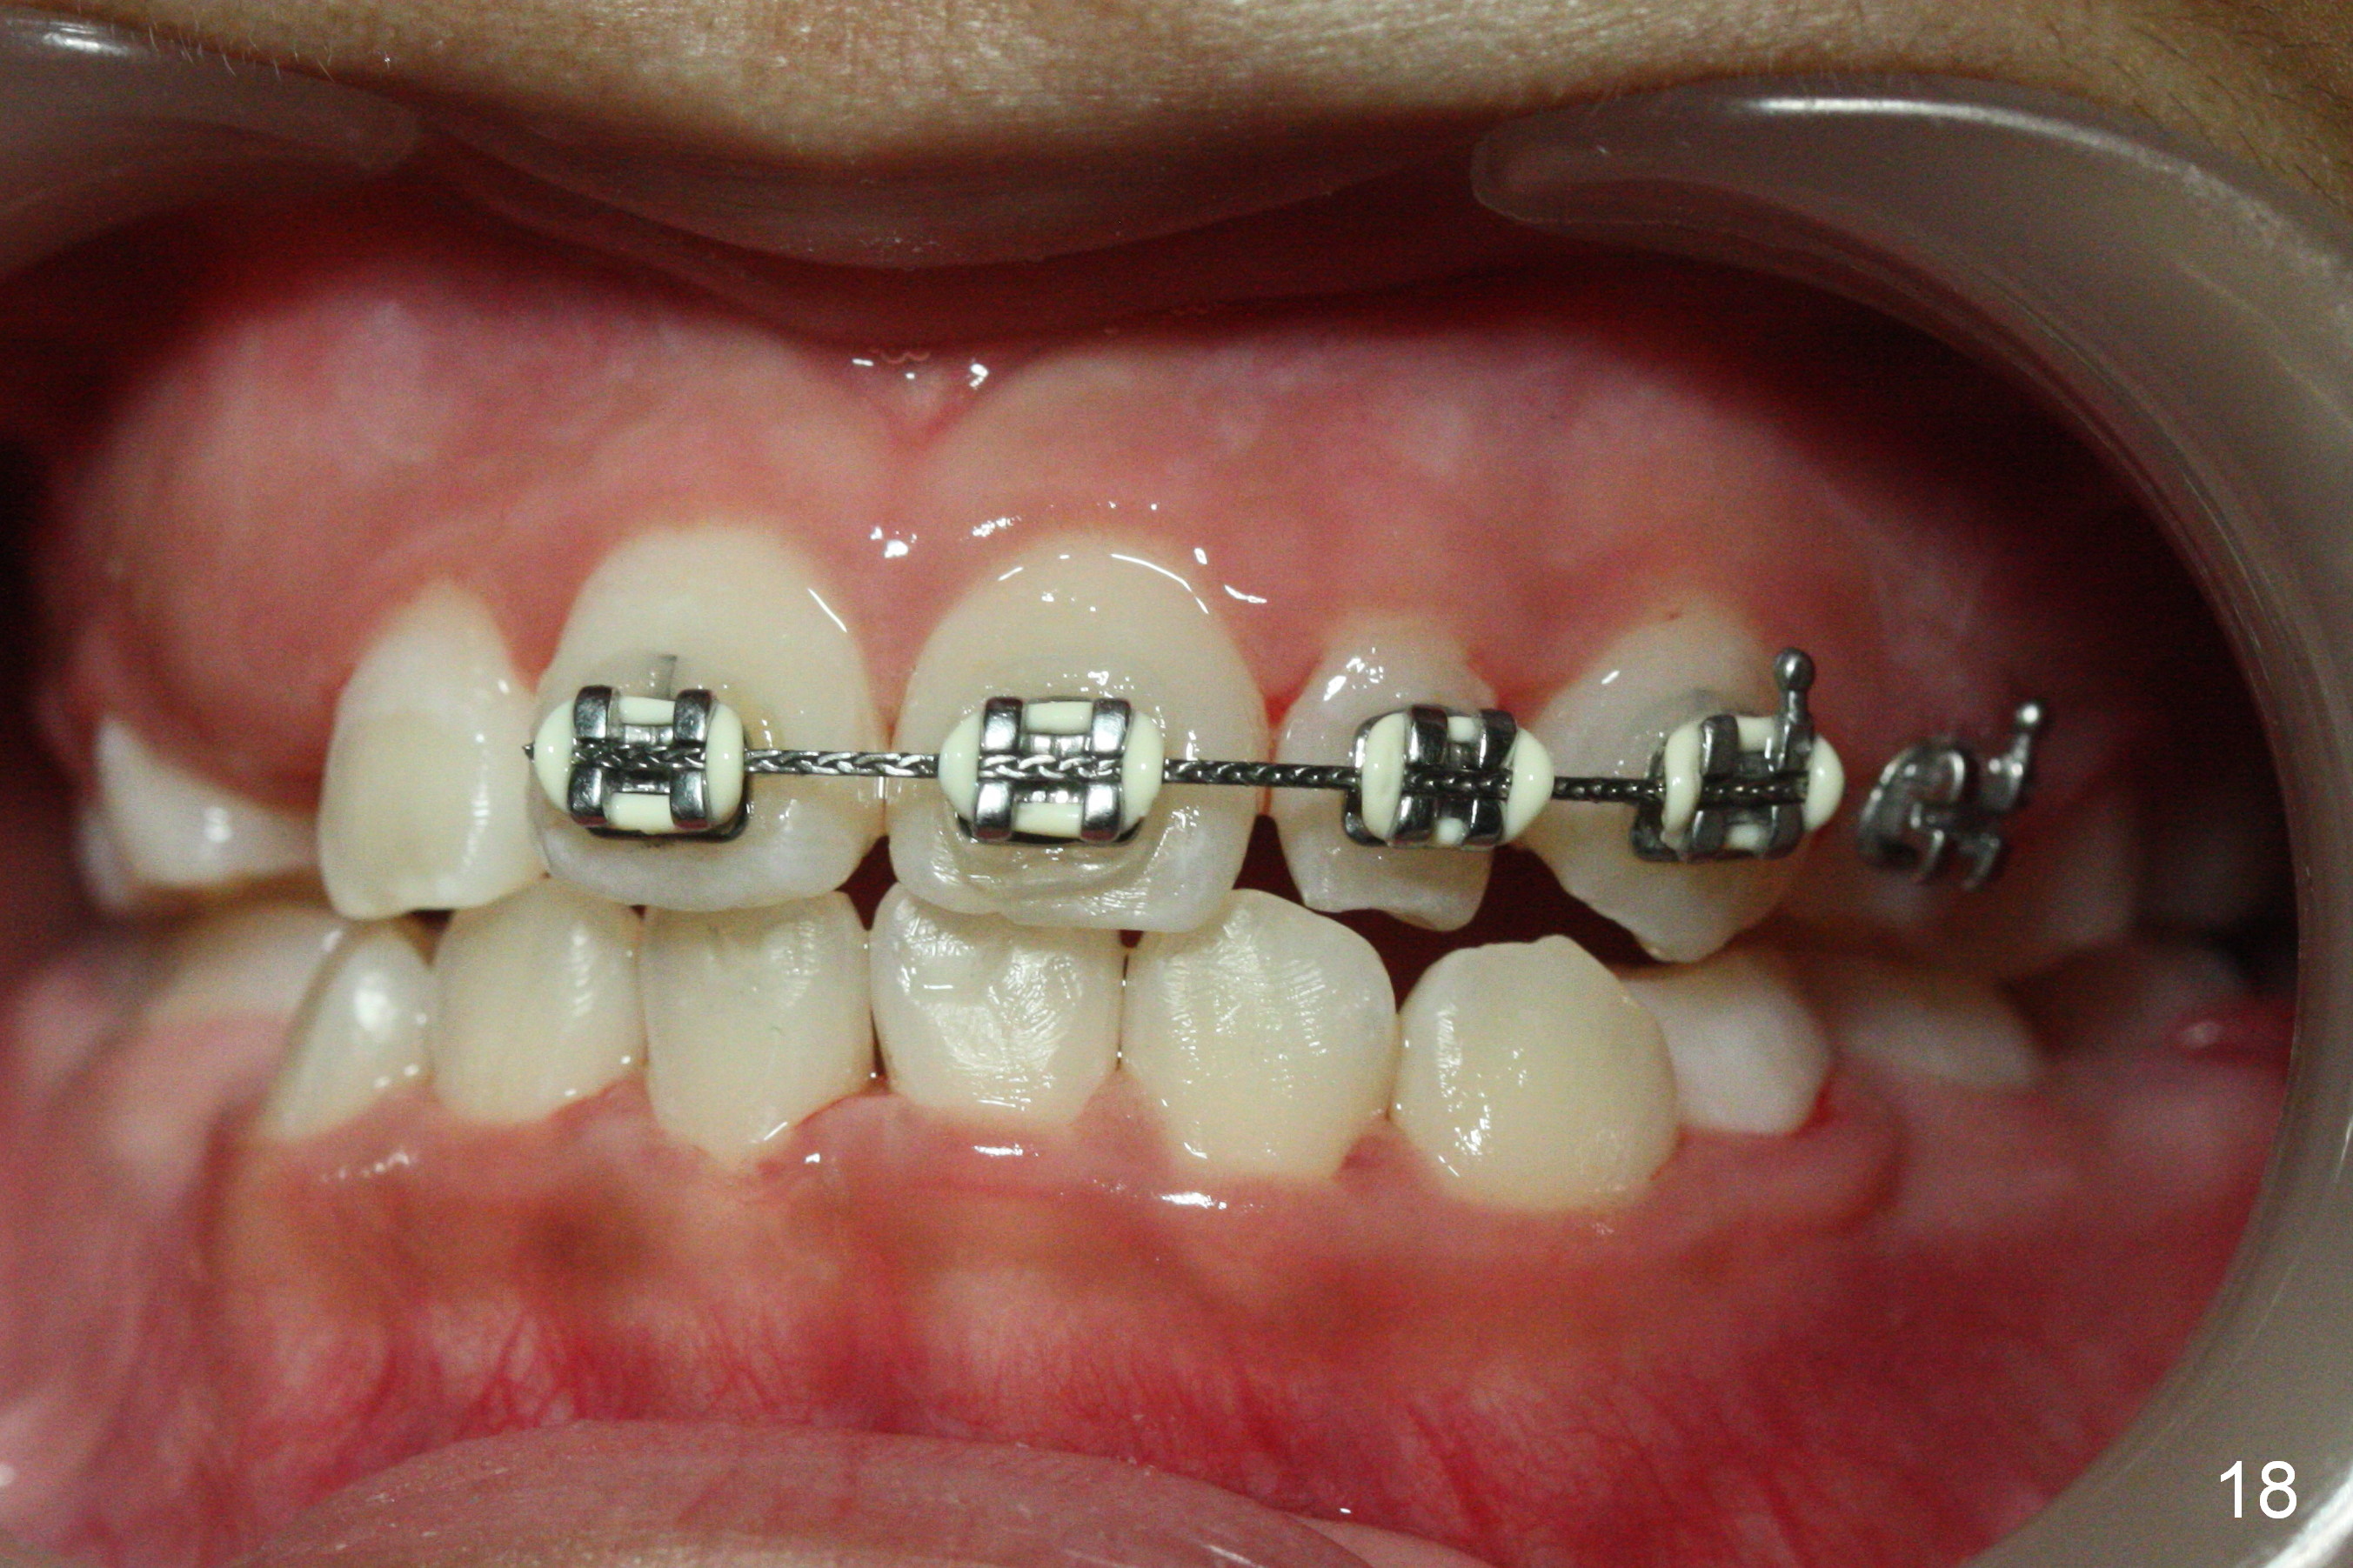

OK Xin, just evaluated the case. If she started with the anterior dental crossbite and you are barely over-corrected right now, I would be very comfortable discontinuing treatment. At her age, there is nothing that can no longer be dealt with beautifully when it is more age appropriate.When anterior cross bite is corrected 19 months post banding, the tooth #10 (microdontia) has tendency of edge-to-edge (Fig.16,17). Power chains are used to create space for #11 to erupt fully before bracketing. In spite of the effort, the peg lateral remains edge-to-edge 23 months post banding (Fig.18,19). The segmental 19x26 braided wire retains as a retainer to prevent #10 from cross bite. The facial profile is more or less normal immediately post debracketing (Fig.20). The anterior occlusion appears to remain basically the same 7 months post debracketing (Fig.21,22). UR3 erupts, while the diastema mesial to UL2 enlarges so that the arch wire appears shorter. UL2,3 appear to be in cross bite 14 months post debracketing, while Es retain at the age of 13 (delayed development, Fig.23).